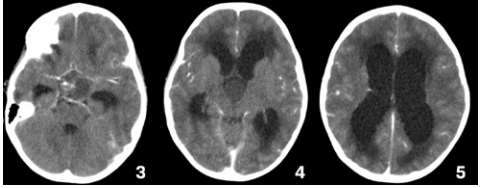

Caso clínico 3 para as questões 27 e 28.

Criança feminina, 04 anos, é encaminhada de Unidade de Pronto Atendimento (UPA) de Olinda-PE com história de cefaleia acompanhada de vômitos, inapetência e sonolência há 03 dias, sendo solicitado parecer da neurocirurgia. Ao exame: ECG Pediátrica de 13 (Resposta Ocular = 3 + Resposta Verbal = 4 + Resposta Motora = 6), isocórica e RFM lentificado bilateralmente, mobilizando todos os membros e reflexos presentes e simétricos.

Seguem, abaixo, as imagens de TC de crânio sem e com contraste da paciente, com índice de Evans de 0,41.

Como se calcula o índice de Evans que foi de 0,41 e o que se fazer pela urgência nesse caso, respectivamente?